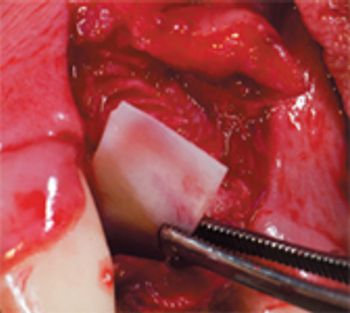

Sorting through your choices for repairing these deep-seated defects.